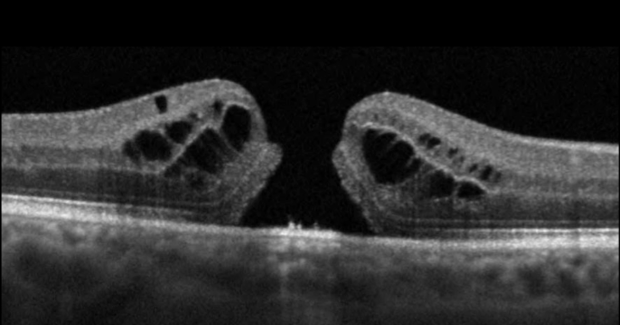

3. Cystoid Macular Edema (CME)

Cystoid macular edema (CME) is a condition in which fluid accumulates in the macula, causing swelling and blurred central vision. CME is often a complication of other retinal conditions like diabetic retinopathy, macular degeneration, or after eye surgery such as cataract surgery. Symptoms include:

Blurry or fluctuating central vision

Distorted or wavy lines

Sensitivity to light

CME can often be managed with medications such as steroids or anti-VEGF injections, which reduce swelling and improve vision. If the condition persists, additional treatments or surgery may be required.

Optical Coherence Tomography (OCT): This non-invasive imaging test provides detailed cross-sectional images of the retina to detect swelling, fluid, or retinal tears.